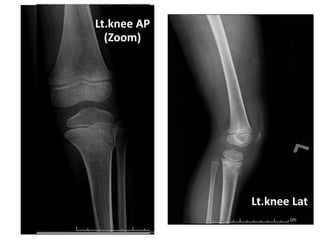

Radiographic findings

Lt.knee AP

Lt.knee Lat

(Zoom)